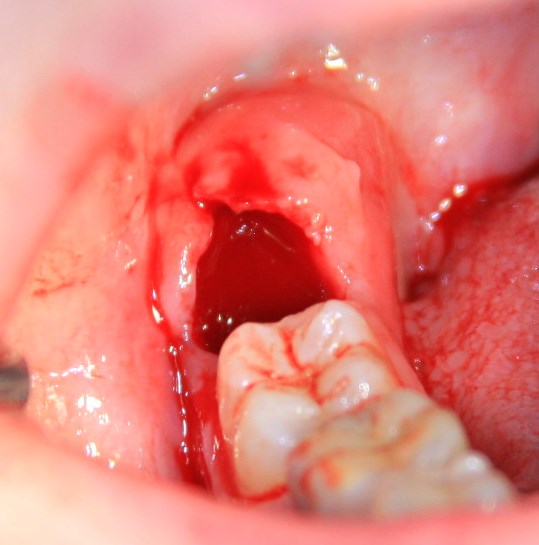

Иными словами, перикоронит может случиться в области любого из зубов, но по стечению обстоятельств, чаще всего случается в области зубов мудрости. Тут я особо подчеркну, что

развитие перикоронита отнюдь не всегда связано с их прорезыванием и нередко происходит уже после него.

Как на картинке ниже: вроде, восьмерка прорезалась давно, но в окклюзионный контакт в антагонистом не вошла. Из-за этого остался десневой капюшон над коронковой частью, усугубленный костным карманом за зубом мудрости. В таких условиях перикоронит случится обязательно — мы только не можем сказать, когда именно.

Поскольку сам человек не в состоянии «промыть» образовавшуюся полость, да и само «промывание» обладает лишь кратковременным эффектом, инфекционно-воспалительный процесс распространяется далее, причиняет дискомфорт пациенту и представляет существенную угрозу для жизни и здоровья.